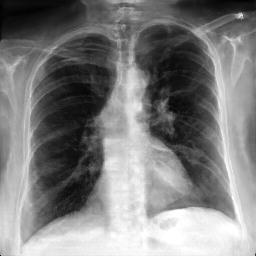

Refer to caption

Train

Valid

(a)XR(a)X_{R}

Test

(b)X^R(b)\hat{X}_{R}

(c)XA:ut(c)X_{A}:\mathcal{L}_{ut}

id\mathcal{L}_{id}

ut+id\mathcal{L}_{ut}+\mathcal{L}_{id}

Fig. 3: Anonymization results. Real images XRX_{R} randomly selected from the training, validation, and test sets are displayed in the first column. The corresponding reconstructed images X^R\hat{X}_{R} are displayed in the second column. The anonymized images XAX_{A} are displayed in the last three columns.

Qualitative Results The visualization results are shown in Fig. 3. In this figure, the anonymized images optimized using only the utility loss ut\mathcal{L}_{ut} (column 3) exhibit greater visual similarity to their real counterparts (column 1), while those optimized using only the identity loss id\mathcal{L}_{id} (column 4) appear more distinct from their originals. Additionally, the anonymized images optimized with both the ut\mathcal{L}_{ut} and the id\mathcal{L}_{id} (column 5) strike a balance, appearing more realistic by simultaneously considering both identity removal and utility preservation.